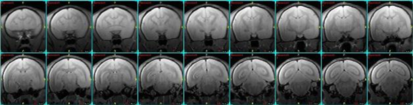

コモンマーモセットの脳の画像

コモンマーモセットの前額断T2強調画像